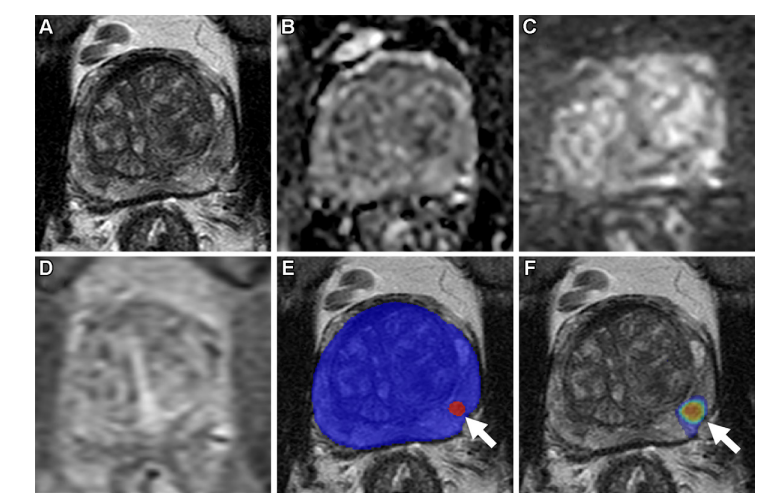

Figure 4 illustrates axial multiparametric MRI findings in a 64-year-old male with elevated prostate-specific antigen levels. The T2-weighted images demonstrated parenchymal changes, while the apparent diffusion coefficient maps revealed areas of reduced water diffusion. High-b-value diffusion-weighted imaging highlighted regions with increased axonal integrity at b = 1500 sec/mm². Dynamic contrast-enhanced imaging demonstrated perfusion heterogeneity across multiple time points (frame 45 of 54 acquired at 5.6-second intervals). Additionally, T2-weighted images were augmented with AI-generated prediction maps, where red contours indicated predicted prostate abnormalities and blue outlines delineated AI-aided organ segmentation. Another T2-weighted image overlaid an AI probability map, with red shading signifying higher likelihood of malignancy. A radiologist’s evaluation using the Prostate Imaging Reporting and Data System (PIRADS) category 1 criteria confirmed no suspicious lesions. However, an AI algorithm identified a false-positive lesion in the left midgland peripheral zone (arrowheads in Figures E and F), which was later confirmed as a misdiagnosis based on gold-standard radiological findings. Core needle biopsy from this region confirmed a Gleason score of 7 (3 + 4), corresponding to prostate adenocarcinoma diagnosis.

图4: 一名64岁男性的轴向多参数MRI扫描显示:血清前列腺特异性抗原(PSA)水平为8.1 ng/mL;(A) T2加权回声图像;(B) 表观扩散系数分布图;(C) 高b值扩散加权图像(b值为1500 sec/mm²);(D) 动态对比增强图像(使用5.6秒间隔采集的54帧中的第45帧);(E) 基于AI预测的T2加权图像(红色轮廓表示AI预测阳性区域;蓝色轮廓为AI对前列腺器官分割的结果);(F) 基于AI概率图的T2加权图像(红色区域标记更高的诊断可能性)。经核磁共振检查未发现显著病变区域。AI系统识别左侧腺体中部外围区存在异常信号(如图E和F中的箭头所示),根据临床路径标准此病变被判定为假阳性。进一步取自该部位活检组织样本证实为Gleason 7分型(3+4)前列腺腺癌